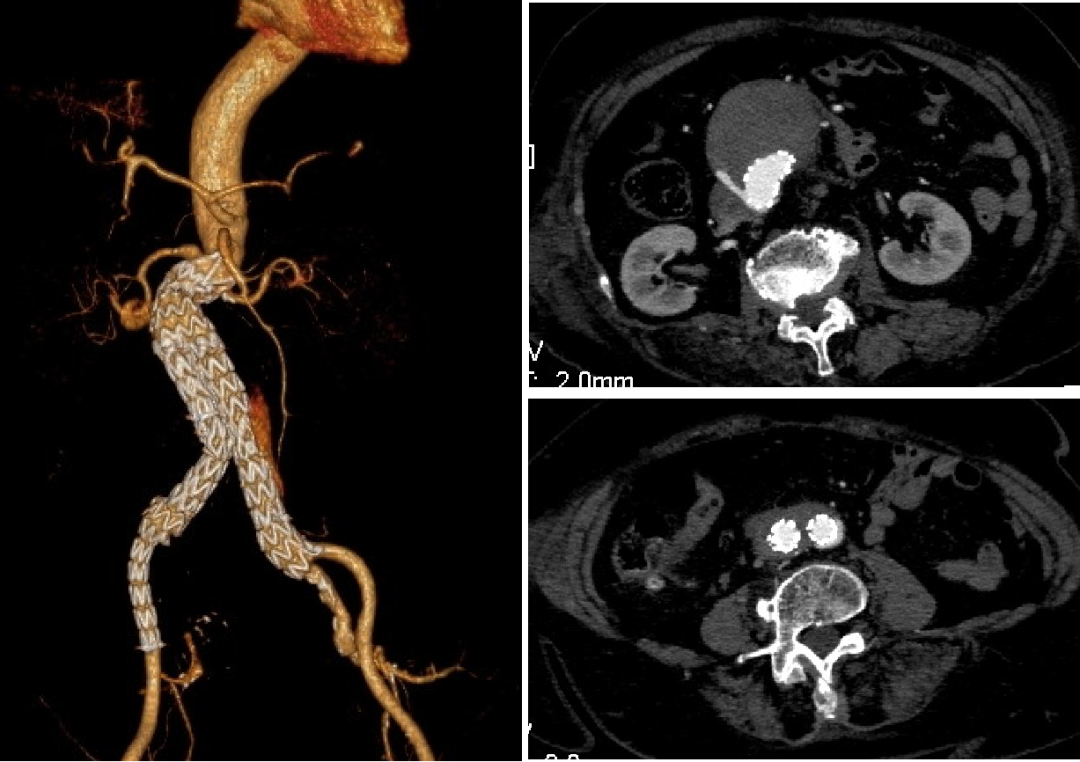

EVAR术后Ia内漏

女性,82岁

体检发现腹主动脉瘤,外院于2018年12月行EVAR术,术后一年,自觉出现腹部搏动性包块,于2020年6月到我院就诊,发现Ia内漏

一般状况较差,高血压,冠心病PCI病史

手术方案:

Plan A 开放手术:胸腹联合切口,行动脉瘤切除人工血管置换+全内脏动脉重建

创伤大,手术时间长;患者高龄,心肺功能差,恐难以耐受

Plan B 介入手术:

近端cuff支架植入:裸支架贴壁不良,内部放cuff无法贴壁密封

动脉瘤腔内修复+内脏动脉腔内重建,如何重建?

开窗或分支支架:内脏区成角大,且有裸支架干扰,重建难度极大,且容易内漏

烟囱:左肾、SMA适合,但右肾开口成角大,超选进入困难,且烟囱支架极易闭塞,如何解决?

最终选择Plan C 杂交手术:动脉瘤腔内修复+左肾动脉、肠系膜上动脉烟囱支架重建+右肾自体肾移植

很好弥补了单纯介入手术的缺点,降低了手术风险,提高了手术成功率

左侧卧位,右侧肋缘下切口,取右肾,保存于灌注液中。将右肾移植于右侧髂窝,右肾动静脉吻合于右侧髂外动静脉

术后5天复查CT

近端I型内漏完全消失

烟囱支架通畅

移植肾显影良好